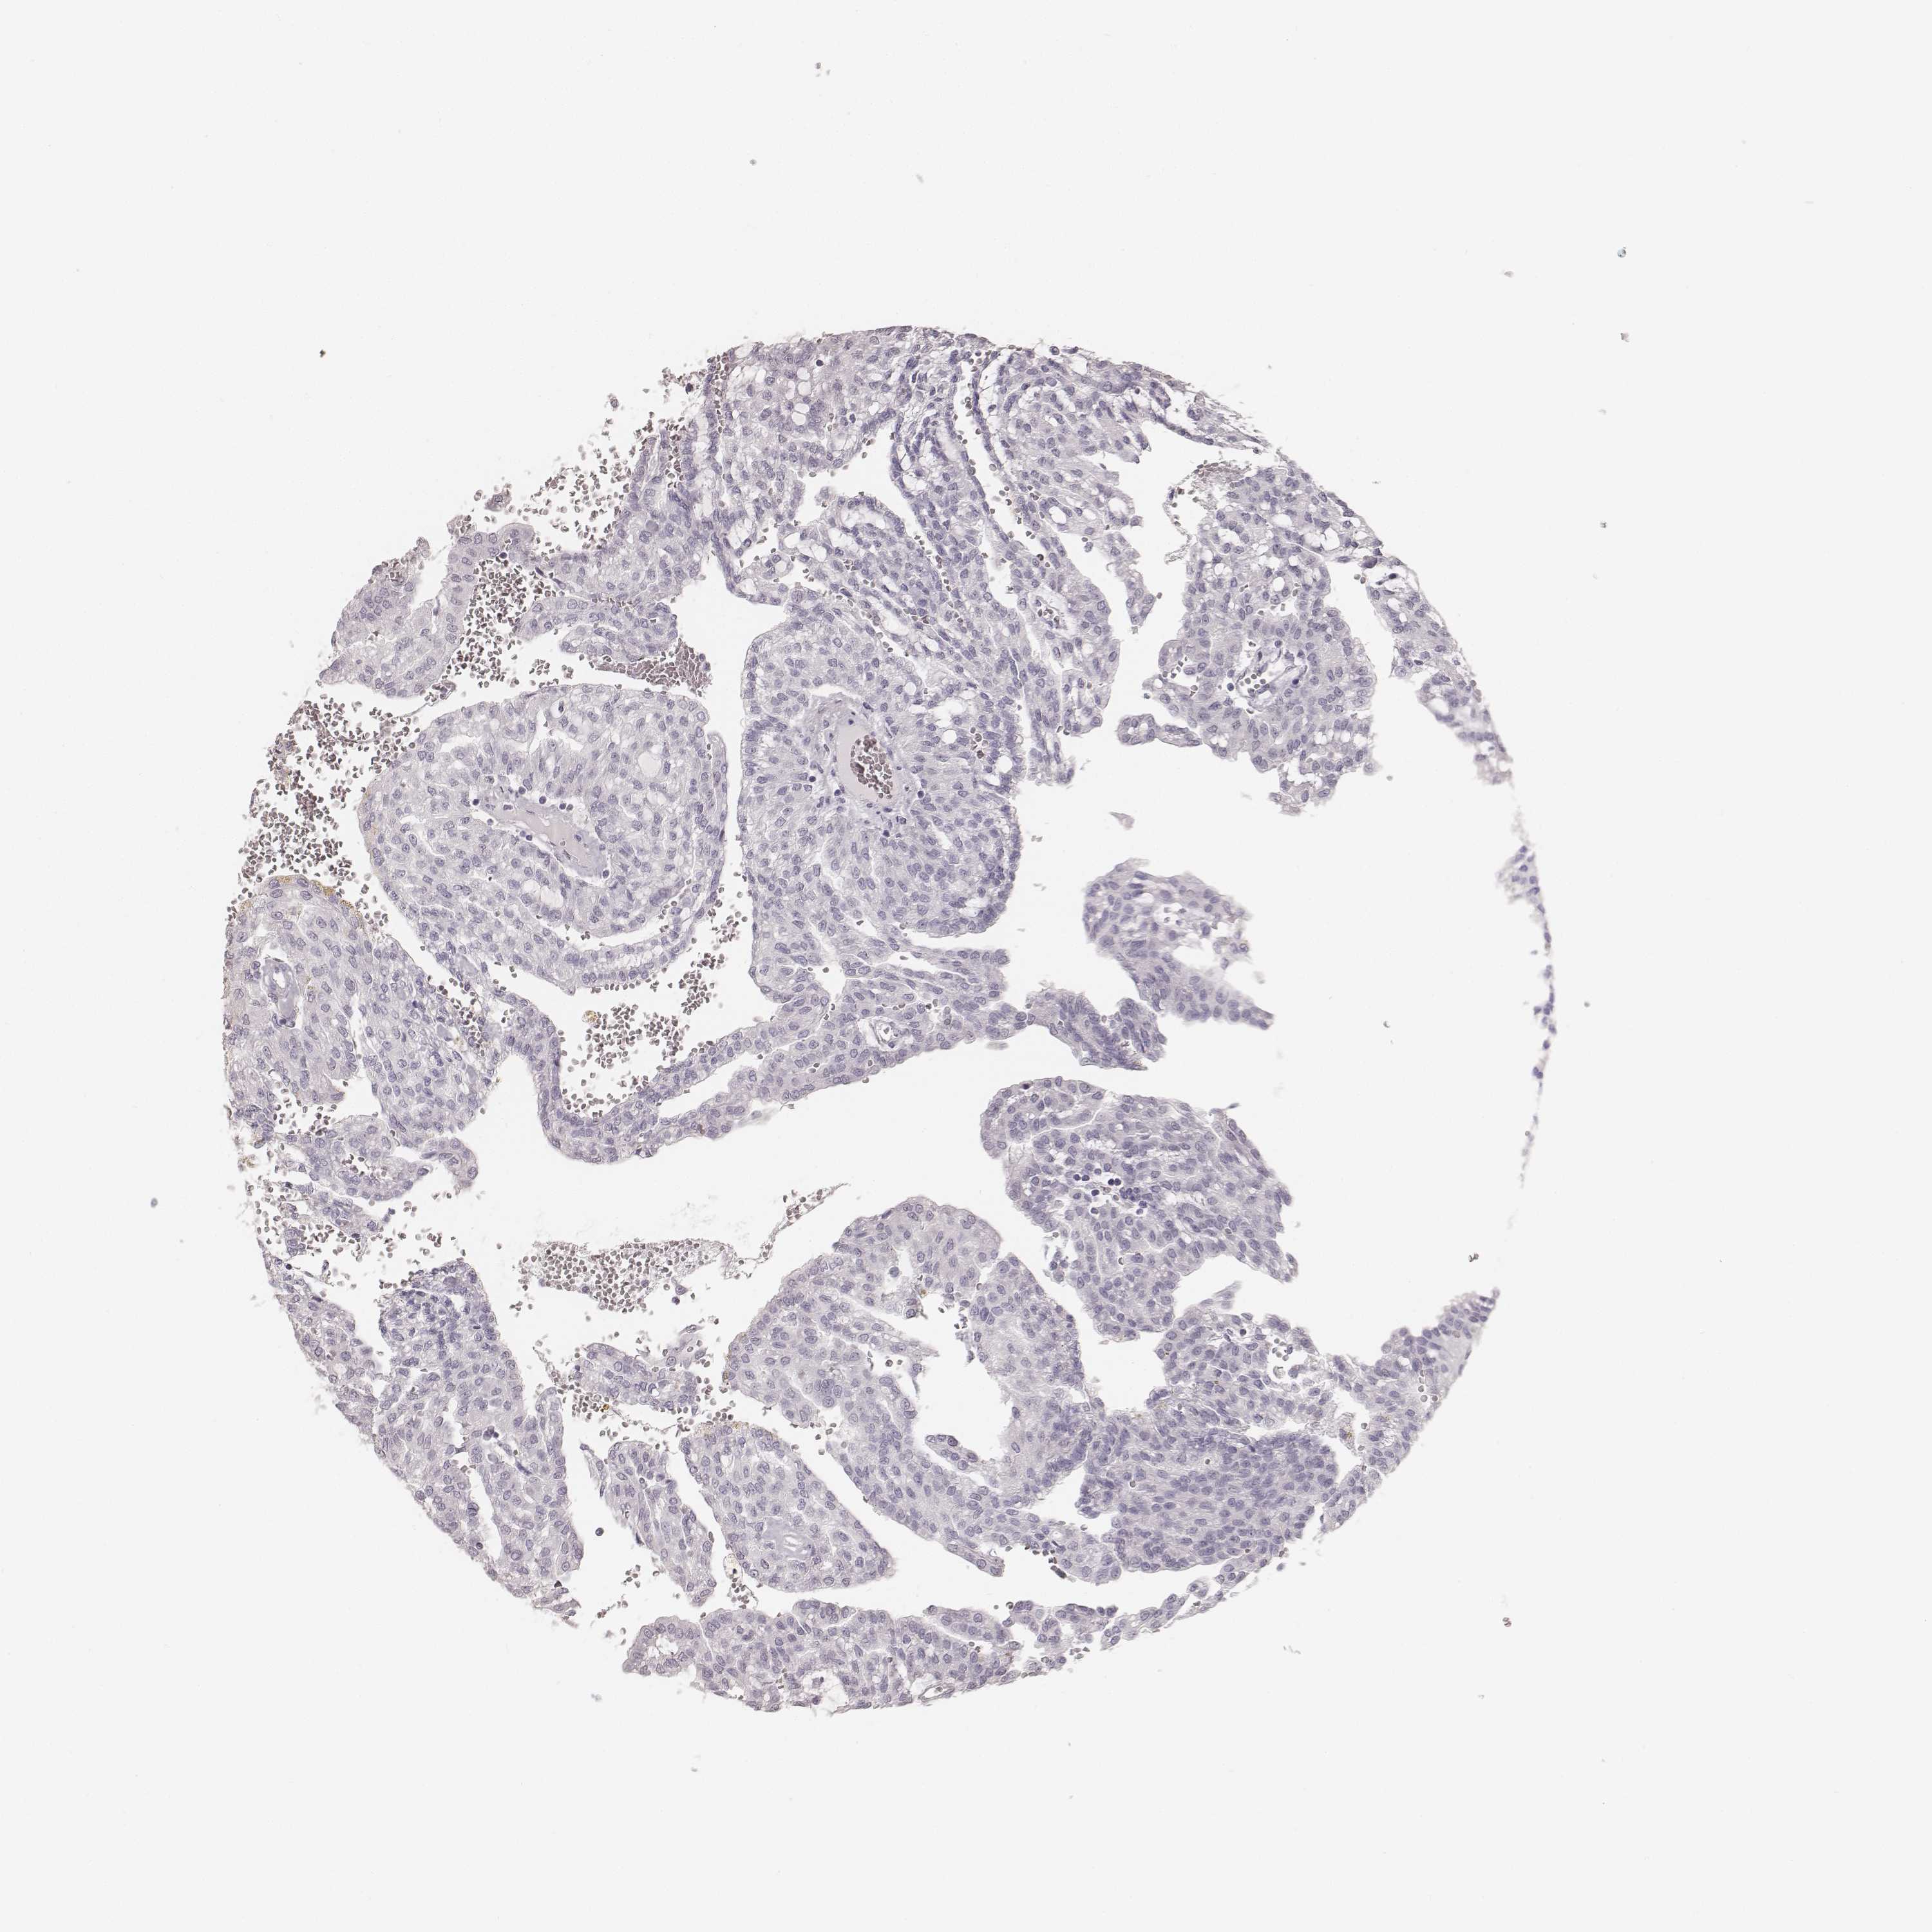

KICH TCGA KIRC TCGA KIRC VALIDATION KIRP TCGA PROTEIN RCC CPTAC PROTEIN EXPRESSION

KIDNEY RENAL CLEAR CELL CARCINOMA (VALIDATION) - Interactive survival scatter ploti

The Survival Scatter plot shows the clinical status (i.e. dead or alive) for all individuals in the patient cohort, based on the same data that underlies the corresponding Kaplan-Meier plots. Patients that are alive at last time for follow-up are shown in blue and patients who have died during the study are shown in red.

The x-axis shows the expression levels (FPKM) of the investigated gene in the tumor tissue at the time of diagnosis. The y-axis shows the follow-up time after diagnosis (years). Both axes are complimented with kernel density curves demonstrating the data density over the axes. The top density plot shows the expression levels (FPKM) distribution among dead (red) and alive patients (blue). The right density plot shows the data density of the survived years of dead patients with high and low expression levels respectively, stratified using the cutoff indicated by the vertical dashed line through the Survival Scatter plot. This cutoff is automatically defined based on the FPKM cutoff that minimizes the p-score. The cutoff can be changed by dragging the vertical line or by entering a cutoff value in the square labeled "Current cut-off".

Under the Survival Scatter plot the p-score landscape (black curve; left axis) is shown together with dead median separation (red curve; right axis). Dead median separation is the difference in median mRNA expression between patients who have died with high and low expression, respectively. It is calculated as follows: median FPKM expression of dead patients with high expression - median FPKM expression of dead patients with low expression. This is intended to aid the user in visually exploring custom cutoffs and the associated p-scores and dead median separation.

Individual patient data is displayed and can be filtered by clicking on one or more of the category buttons on the top of the page. Categories describing expression level and patient information include: high, low, alive, dead, female, male and tumor stages. The scale of the x-axis can be toggled between linear and log-scale by clicking on the "x log" button. Mouse-over function shows TCGA ID, patient information and mRNA expression (FPKM) for each patient.

& Survival analysisi

Kaplan-Meier plots summarize results from analysis of correlation between mRNA expression level and patient survival. Patients were divided based on level of expression into one of the two groups "low" (under cut off) or "high" (over cut off). X-axis shows time for survival (years) and y-axis shows the probability of survival, where 1.0 corresponds to 100 percent.

Survival analysis data not available.

TCGA RNA samplesi

RNA-seq data is reported as average FPKM (number Fragments Per Kilobase of exon per Million reads), generated by the The Cancer Genome Atlas (TCGA) .

Normal distribution across the dataset is visualized with box plots, shown as median and 25th and 75th percentiles. Points are displayed as outliers if they are above or below 1.5 times the interquartile range. FPKM values of the individual samples are presented next to the box plot.

Average pTPM 0.0

Number of samples 100